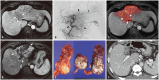

Yttrium-90 transarterial radioembolization (TARE) has emerged as a valuable treatment option for hepatocellular carcinoma (HCC) and is being increasingly incorporated into clinical guidelines. Recent advancements in dosimetry, including personalized dosimetry and multi-compartment modeling, have significantly improved tumor response and clinical outcomes. Although high tumor-absorbed doses are associated with better oncologic control, careful dose adjustment is essential for minimizing toxicity to normal liver tissue and lungs. This review explores the key aspects of TARE dosimetry, including single- and multi-compartment modeling, differences between resin and glass microspheres, dose-response relationships, and strategies to mitigate hepatotoxicity and radiation pneumonitis. Various clinical applications of TARE have been discussed, ranging from curative-intent radiation segmentectomy and lobectomy to palliative treatment of diffuse and macrovascular invasion-associated HCCs. In South Korea, where cadaveric liver transplantation is limited, a multidisciplinary approach is particularly important for optimizing treatment strategies and preserving liver function for potential future interventions. As dosimetry continues to evolve, further research is required to refine dose optimization protocols and validate their clinical impact in different patient populations, including those in South Korea.